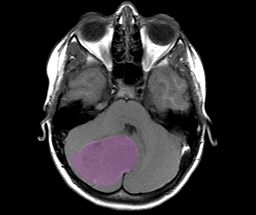

MRT-Darstellung eines Medulloblastoms. (© DKFZ)